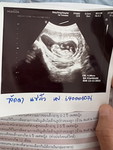

คัดกรองดาวน์ซิน# โดมได้ 1:260 #คุณแม่ๆช่วยแนะนำหน่อยค่ะ ตอนนี้เครียดมาก เขาไม่ได้ส่งเจาะน้ำคร่ำ บ้านนี้ไม่ได้ส่งเจาะน้ำคร่ำเลย แม่ๆคนไหนได้เจาะน้ำคร่ำเพิ่มไหมค่ะ กังวลว่าลูกจะเป็นอะไร ปรกติกำหนดเท่าไหร่ค่ะถึงมีความเสี่ยงเป็นดาวน์